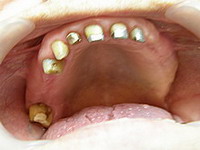

Situatie initiala

Proteza scheletata